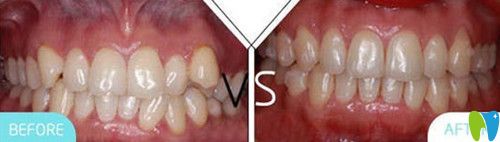

二、牙齒矯正案例:

術(shù)前牙齒癥狀:牙列不齊

術(shù)后牙齒效果:歪斜的牙齒立正了

凱樂(lè)口腔牙齒矯正前后對(duì)比圖